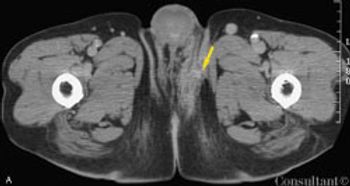

An obese 55-year-old woman had intermittent dysuria and frequent urination for 4 days and fever, abdominal pain, and vomiting for 3 days. Her history included type 1 diabetes mellitus, hypertension, and angina; her medications included insulin, nifedipine, and nitroglycerin.